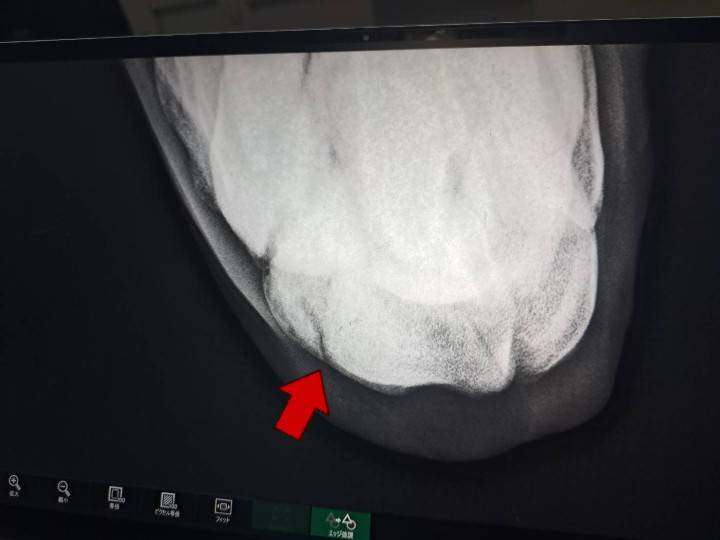

本馬は3戦のみのキャリアの浅い3歳馬です。前走のレース後に左前脚の膝に亀裂骨折を発症していることが判明し、6ヶ月の見舞金支給対象となったため、この度オークションに上場することになりました。2戦目の阪神・ダート1200m戦では上がり最速のタイムで追い上げており、また、先週12日の園田の交流戦では2着となっているので、回復を待って地方競馬で出走させていけば結果を出せるものと思われます。

※2023年4月12日に左前第3手根骨亀裂骨折を発症。事故見舞金9号(競走中の事故により事故発生の日から6ヵ月以上出走できなくなった場合)の適用を受けています。